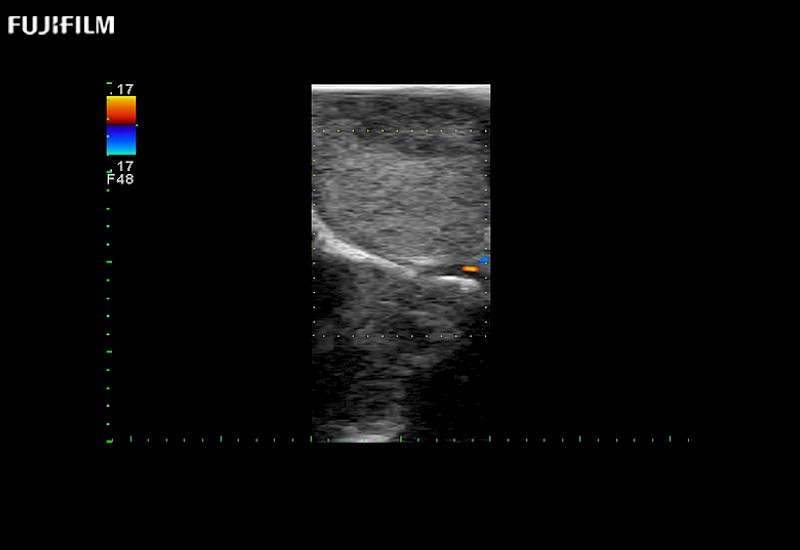

Hockey-stick linear array transducer is the transducer of choice for cervical spine scanning.

Main Specifications: